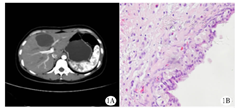

患者女性,39岁,4月余前体检发现肝左叶占位性病变,因伴有月经相关的周期性肝区疼痛症状,于2018年5月1日就诊于吉林大学第一医院;既往剖宫产手术史11年,平素月经规律,无痛经史;否认子宫内膜异位症、流产、病毒性肝炎等病史。查体:腹部平坦,未见腹壁静脉曲张、胃肠型及蠕动波,脐下3 cm处可见一长约13 cm的正中竖行手术瘢痕;上腹部轻压痛,无反跳痛及肌紧张,未触及明显包块,肝脾肋下未触及,胆囊未触及,墨菲征阴性,Courvoisier征阴性。肝肾区无叩痛,腹部叩诊呈鼓音,移动性浊音阴性,肠鸣音约3次/min。实验室检验:肝功能、肾功能、外科综合、血常规、肿瘤标志物及余检验指标均无异常。影像检查:超声检查示:肝左叶可探及一大小约61 mm×53 mm低回声团块,诊断为肝囊性占位性病变。肝胆胰多排CT平扫+三期增强检查所见:肝体积不大,表面光滑,肝门肝裂不宽,各叶比例协调,肝左叶内侧段见不规则囊状低密度,大小约6.5 cm×5.1 cm,界清,病变内见分隔,增强扫描分隔可见强化,邻近胆管稍扩张。胆囊不大,壁稍厚,腔内未见异常密度影,胆总管未见扩张,胰腺及脾脏形态、大小及密度未见异常,胰管未见扩张。检查诊断:考虑肝左叶内侧段囊性占位性病变,考虑良性,待除外囊腺瘤(图1A)。

临床诊断:肝囊性占位性病变,考虑囊腺瘤。因患者及家属手术意愿强烈,于2017年5月4日行剖腹探查术。术中见肝左内叶一枚大小约6.8 cm×6.0 cm囊性肿块,突出肝脏表面,质地柔软,有完整包膜,与周围肝组织边界清楚。因无法确定肿物性质,遂完整切除肿物并送快速病理,回报考虑肝脏子宫内膜异位囊肿,未行扩大手术。术后病理诊断同术中快速病理结果,免疫组化示:PR(+),ER(+),见图1B。临床诊断为肝脏子宫内膜异位症(hepatic endometriosis,HEMs)。患者术后第5天康复出院,半年后复查无肿瘤复发及血清学指标异常。